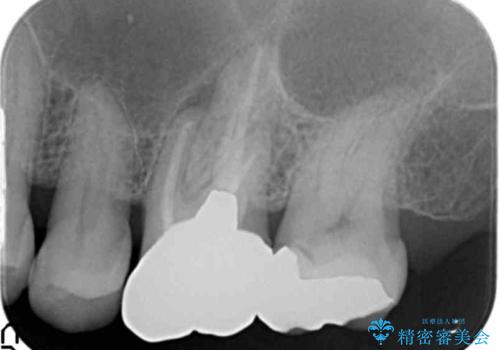

奥歯(左上7)のメタルインレー(銀の詰め物)を除去し精査したところ、奥歯はわれていました。

根尖近くまで深くヒビが入っており保存不可能な状態でした。

上顎洞が近接しており上顎骨の厚みが薄いことから、ソケットリフト(上顎洞底挙上術)をインプラント埋入と同時に行いました。

ソケットリフトにより上顎洞底を挙上し骨造成することにより、骨の厚みが薄い部分でもインプラントが可能になります。